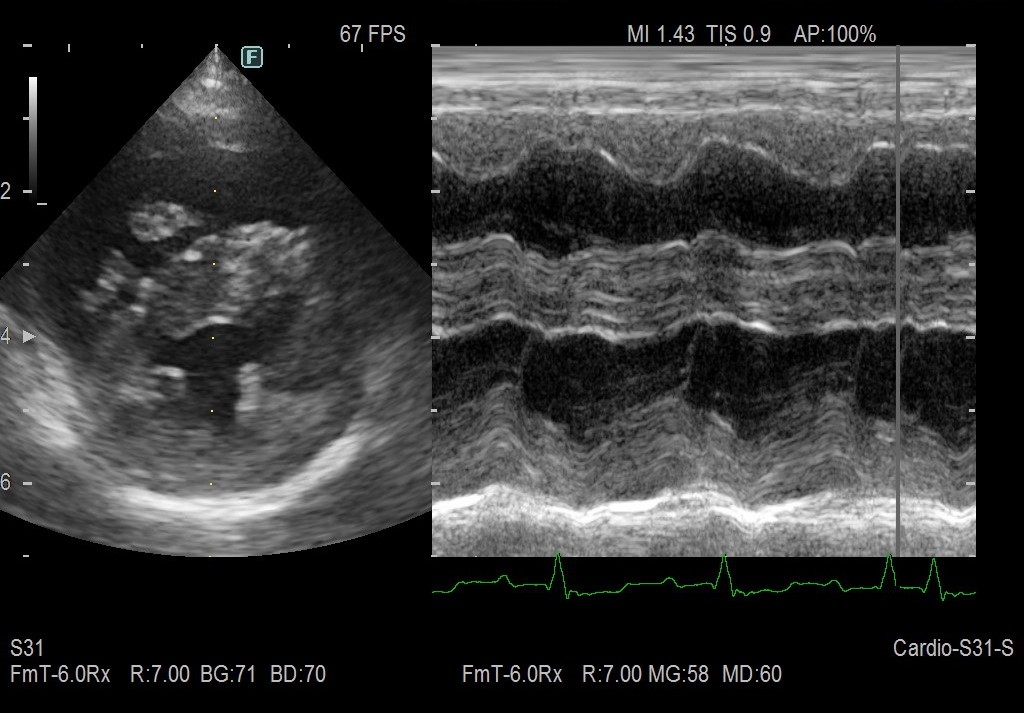

本稿トップのエコー画像は、下の円形部分が左心室で、その上の黒い部分が右心室内腔です。右心室が肺に血液を送り出す部分ですから、ホースの基部だと考えるとわかりやすいかと思います。

風船(肺)に血液を送りこめないので、ホースの基部(右心室)がパンパンに拡張して左心室を圧排しています。

左が治療前、右が治療後の画像です。